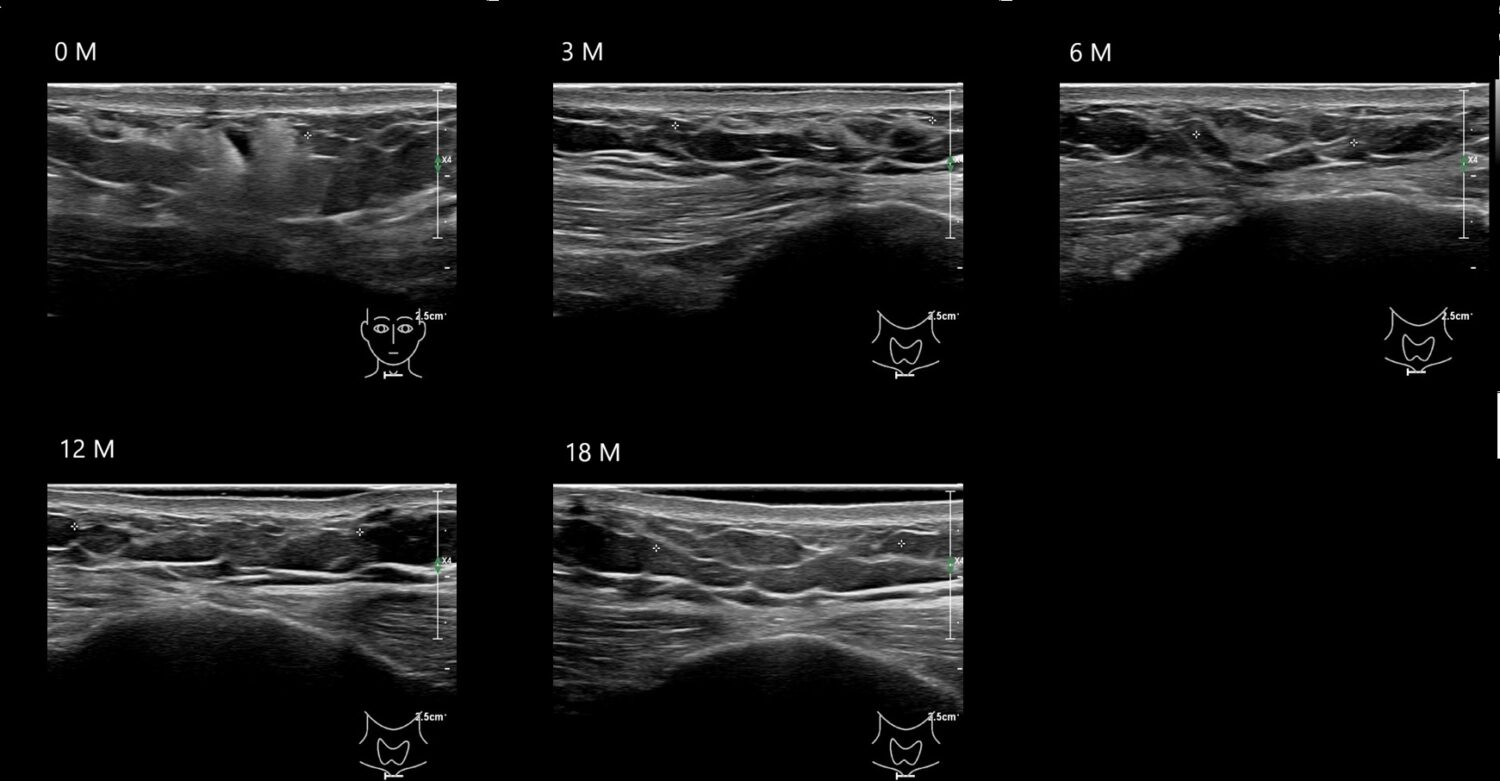

Fillers

Draw in the image on the right where the fillers are located. To check if your answer is correct, please click on the secondary image.